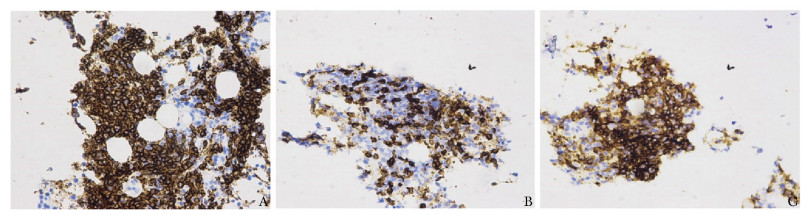

• 摘要: Evans综合征是指同时或相继发生自身免疫性溶血性贫血和免疫性血小板减少症,依据病因可分为原发性和继发性两种,其中血液系统恶性肿瘤是较为常见的继发因素。现报道1例特发性Evans综合征病例,首次起病时排除了可能的继发因素,经利妥昔单克隆抗体联合硼替佐米治疗后病情改善,1年后再次发病并最终确诊为小B淋巴细胞淋巴瘤,提示对于复发或难治性Evans综合征,应仔细筛查相关继发因素。本文通过分析此患者疾病复发过程、实验室检查结果、诊治经过,以期为临床医师诊治该类疾病提供帮助。

Abstract: Evans syndrome is defined by the simultaneous or sequential development of autoimmune hemolytic anemia and immune thrombocytopenia, which is classified as primary or secondary. Hematological malignancy can be a common secondary underlying disease. Here we report a case presenting as primary Evans syndrome after excluding all possible secondary disorders. Evans syndrome improved after treatment of rituximab combined with bortezomib. One year later, the symptoms relapsed and small B-cell lymphocytic lymphoma was eventually diagnosed. The recurrence of disease, laboratory examinations, diagnostic process, and treatment were analyzed and discussed not only to remind clinicians that secondary factors should be re-evaluated in recurrent or refractory Evans syndrome, but also to provide help for clinicians to diagnose and treat such diseases. It is often necessary to remove the secondary factors in secondary Evans syndrome so that the disease can be effectively controlled.